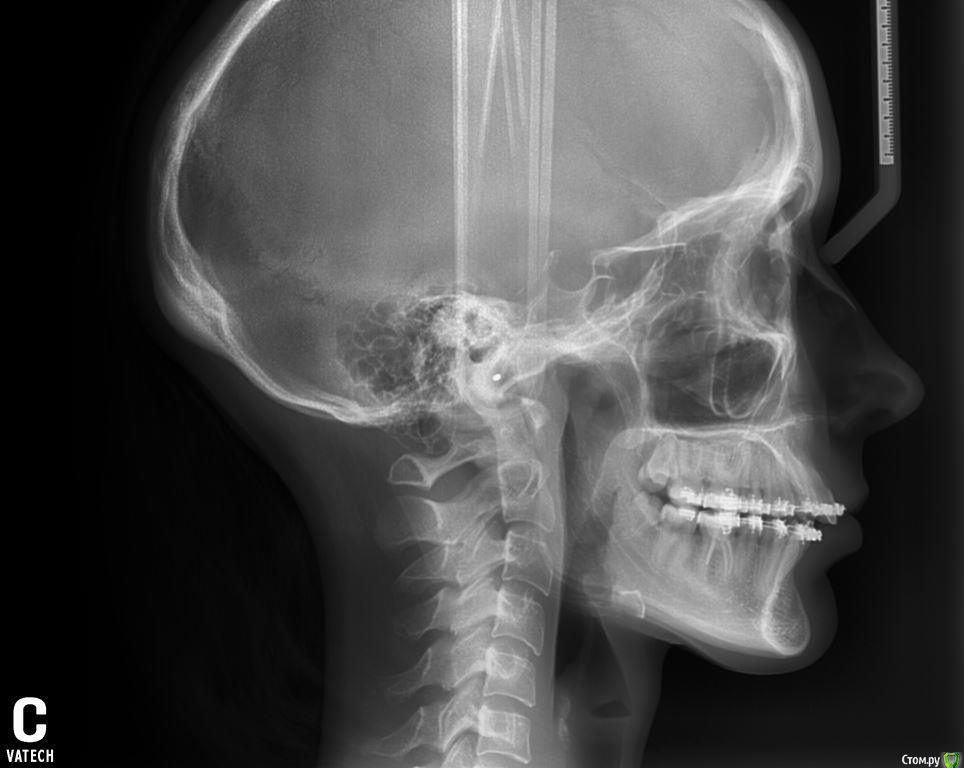

Айсылу Опубликовано 23 июля, 2015 Автор Поделиться Опубликовано 23 июля, 2015 Здравствуйте. Снова я с вопросом к Вам, уважаемые, ортодонты. Вот сделала такие снимки. Ортодонт из "Большого города" сказал, что суставные головки на месте и что выдвигать нижнюю челюсть нельзя. Расширять НЧ уже поздно, из-за возраста. Три варианта решения проблемы мне предложили.:1. Удалить 4-ки (предупредил, что удаление приведет к деформации черепа);2. Хирургическим путем (на этот метод я никогда не решусь);3. снять брекеты. Я записалась на снятие. Для успокоения души решила еще и Ваше мнение узнать... Единственное меня беспокоит тот момент, на сколько губителен этот мой новый дистальный прикус. И что хуже, глубокий прикус, который был до лечения, или же этот, который возник у меня процессе лечения.? Ссылка на комментарий